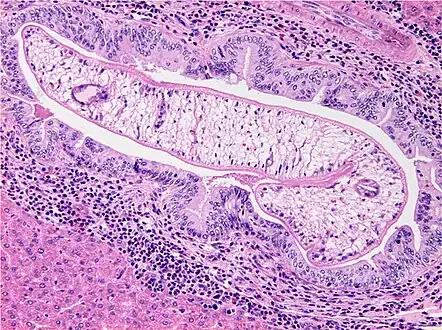

Photomicrograph of an adult O. viverrini in bile ducts of experimentally infected hamster -